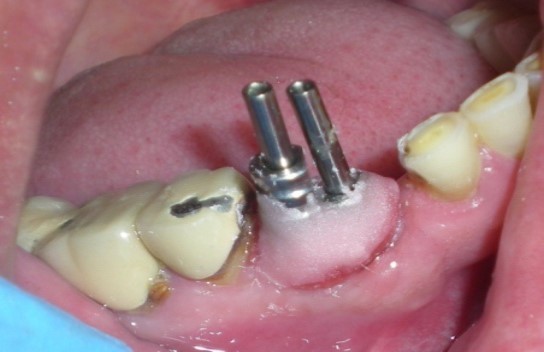

The other impression coping was modified by holding it with artery forcep and cut it with carborundum disc so that it fits properly over the other implant. After modification, it was secured with long connecting/fastening screw to the respective implant. the complete seating of the impression copings was verified with a periapical radiograph.

Insufficient space between two impression copings, preclude the flow of impression material between them, which may lead to movement of the impression coping resulting in an inaccurate impression. To overcome this, the two impression copings were connected with auto polymerizing acrylic resin (Figure 4, Rapid Repair acrylic resin. DPI, India)

Figure 4.Modified impression copings splinted with unmodified coping with autopolymerizing acrylic resin.